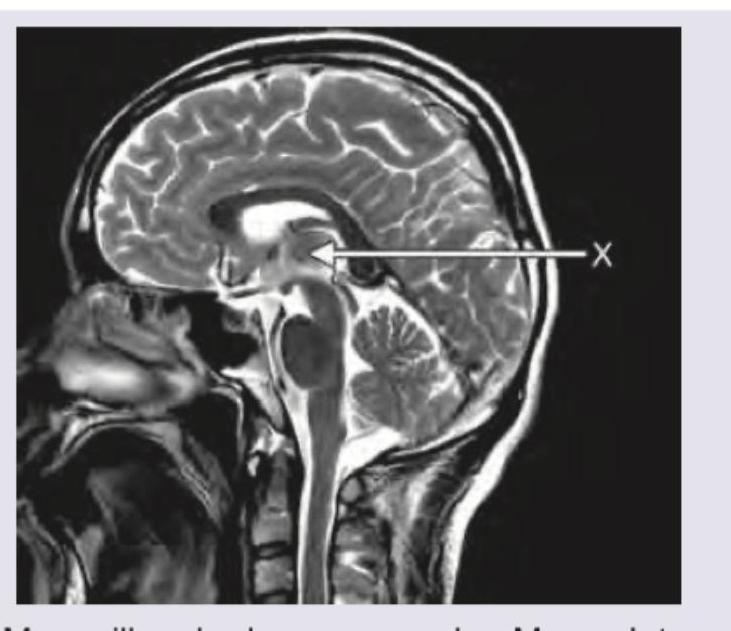

The structure marked as $X$ is:

Explanation: ***Mammillary body*** - The arrow points to a small, rounded structure located on the **ventral surface of the hypothalamus**, characteristic of the mammillary body - Mammillary bodies are part of the **limbic system** and play a crucial role in **memory formation** and **recollection** - These paired structures are visible on midsagittal brain imaging as small rounded projections *Massa Intermedialis* - The massa intermedia (interthalamic adhesion) is a flattened band of tissue connecting the two halves of the **thalamus** across the third ventricle - Located more **superiorly and centrally** within the diencephalon, not ventrally as shown *Pons* - The pons is a larger, bulbous structure located anterior to the **cerebellum** and superior to the medulla, forming part of the brainstem - It is much more **posterior and inferior** to the marked area *Clivus* - The clivus is a **bony structure** at the skull base, formed by the **sphenoid** and **occipital bones** - It is a radiological landmark but represents bone, not brain parenchyma as indicated by the arrow